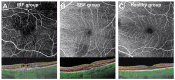

The aim was to analyze the variations in macular vascularization on optical coherence tomography angiography (OCTA) according to the presence of intraretinal fluid (IRF) induced by exudative age-related macular degeneration (AMD). We included exudative AMD patients with IRF and/or subretinal fluid (SRF) and age-matched control eyes. All patients underwent a macular 6 × 6 mm swept-source OCTA. The mean perfusion density (MPD) and mean vascular density (MVD) were calculated in the superficial (SCP) and the deep (DCP) capillary plexus at two timepoints: during an episode of exudation (T0) and after its total resorption (T1). A total of 22 eyes in the IRF ± SRF group, 11 eyes in the SRF group and 11 eyes in the healthy group were analyzed. At T0, the IRF ± SRF group showed significantly lower MPD and MVD than healthy eyes in the SCP (p < 0.001) and DCP (p < 0.001). At T1, MPD and MVD significantly increased from T0 in the SCP (p = 0.027 and p = 0.0093) and DCP (p = 0.013 and p = 0.046) but remained statistically lower than in the healthy eyes. For the SRF group, only the DCP showed significantly lower MPD (p = 0.012) and MVD (p = 0.046) in comparison to the healthy eyes at T0. The present study shows that retinal vascular changes do occur in the case of exudative AMD.